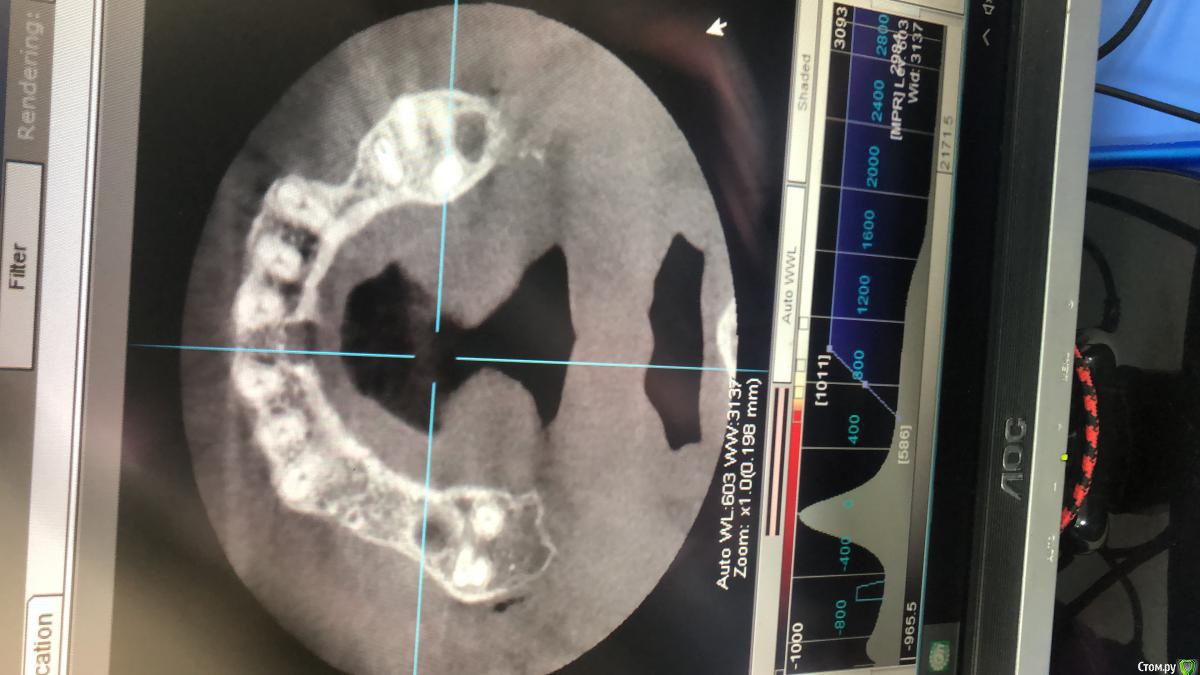

AAbdymomunov Опубликовано 24 июня, 2019 Поделиться Опубликовано 24 июня, 2019 Нужна помощь есть ли альтернатива вместо синуса? Пациент котегорически против синуса! 1 Ссылка на комментарий

vgraev Опубликовано 25 июня, 2019 Поделиться Опубликовано 25 июня, 2019 альтернатива - съемный протез. Вы просто уверенно донесите информацию, что ничего страшного нет в этой операции, риски не большие, и в конечном итоге будет в разы комфортнее,чем со съемником. если пациент чувствует уверенность,которая от доктора исходит, обычно все страхи уходят. бывают ,конечно,исключения))) 1 Ссылка на комментарий